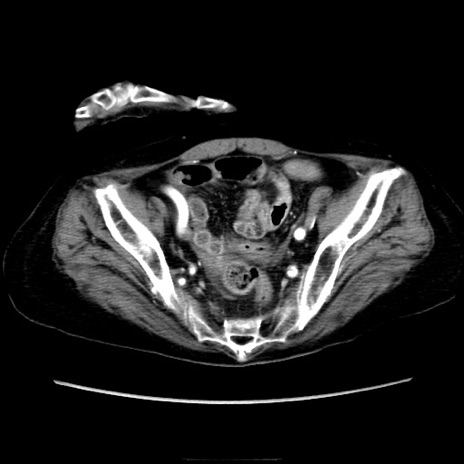

症例40(横断像)

横断像